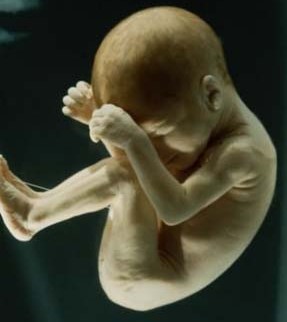

Il bambino ora prende quasi 200 grammi a settimana, pesa circa 1250 grammi e i suoi polmoni continuano ad esercitarsi nella respirazione. La testa cresce per fare spazio al cervello che ogni giorno vede nascere miliardi di nuovi neuroni, scalcia a più non posso ed è possibile contare i suoi movimenti per verificare il suo benessere e controllare che sia ben ossigenato. Per farlo, mettiti sdraiata su un fianco ogni giorno alla stessa ora, rilassati e concentrati su di lui, poi conta quanto tempo occorre al tuo piccolo per farsi sentire almeno dieci volte, conterai calci, pugni, singhiozzi e anche movimenti della testa e del sederino. La buona regola è che non servano più di due ore per arrivare a dieci.

Il bambino continua a crescere e ormai occupa quasi interamente lo spazio nell’utero.È possibile avvertire movimenti netti e precisi, al punto che potresti distinguere bene di quale parte del corpo si tratta, se la testa, il sederino o anche la schiena.

Il bambino è arrivato a circa 1400 grammi, è più cicciottello e la sua pelle è più liscia e rosea.Con le sue continue capriole, potrebbe trovare la posizione definitiva per la nascita.

Ora il piccolo pesa circa 1600 grammi, ogni giorno che passa mette su il grasso sottocutaneo e la pelle è meno rugosa, lo spazio disponibile è poco e i suoi movimenti sono meno “tellurici”.

L’utero è arrivato a circa 12 centimetri sopra la linea ombelicale trasversa e il piccolo pesa circa 1800 grammi ed è lungo circa 40 centimetri.

La peluria che lo ricopre comincia a scomparire mentre la vernice caseosa lo ricopre totalmente. Gli occhi distinguono la luce dal buio e, soprattutto, distingue il caldo dal freddo, al punto tale che si muove se viene posta una fonte di calore vicino alla pancia.